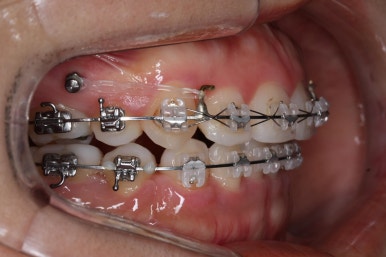

우선 재배열 부터 하였습니다.

브라켓의 위치가 교정을 하는데 있어서 매우 중요하기에 일부분은 먼저 재부착을 하였습니다.

이 후에는 미니스크류를 심어주었어요.

해당 장치를 활용해 윗니를 뒤로 당겨왔습니다.

점점 개선이 되고 있는 모습이 보입니다.

정면으로 맞물렸던 교합도 좋아지고 있으며 이로 인해 자연스레 위아래의 앞뒤 간격도 맞닿게 되고 좁아지고 있습니다.

좌측에서 본 모습도 마찬가지입니다.

발치 후에 남아있던 미세한 공간도 없어졌고 윗니도 후방 이동 되면서 교합이 좋아지고 있습니다.